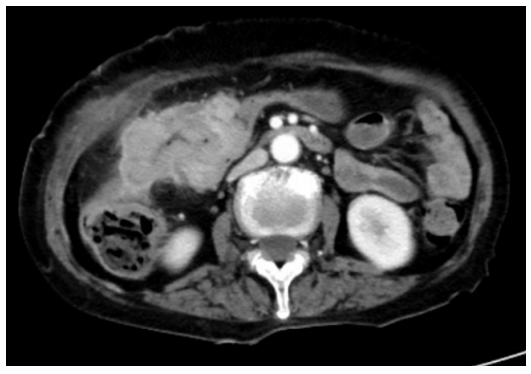

2022年6月20日行结肠镜检查:距肛缘70cm见一肿物,质脆,触之易出血,肠镜无法通过。镜下诊断:升结肠癌。病理会诊(距肛70cm):腺体重度异型增生伴坏死、癌变。免疫组化:IHC:PMS2(+),MSH6(+),MSH2(+),MLH1(+),HER2(1+)。

基因检测:RAS/BRAF野生型,MSS。

2022年6月25日行胸腹部CT检查:横结肠右侧-结肠肝曲肠癌侵犯右侧腹壁全层(最厚处约3.1cm,累及长度约8.8cm),与十二指肠关系密切,伴周围肠系膜多发淋巴结转移。双肺多发小结节,部分磨玻璃结节,建议随诊(大者位于右肺上叶,长径约0.8cm)(图4)。

初步诊断:结肠肝曲癌累及腹壁及十二指肠(结肠肝曲癌 cT4bN+M0);慢性心力衰竭。

患者于2022年7月11日予以TAS-102+贝伐珠单抗双周方案治疗4周期。具体用药方案:TAS-102:35mg/m2/次 p.o. bid d1-5,q2w;贝伐珠单抗:5mg/kg ivgtt 2h d1 q2w。

2022年8月24日行胸腹部CT检查:结肠癌化疗后,病灶范围较前缩小(现最厚处约2.7cm,累及长度约7.4cm),周围肠系膜多发淋巴结转移,较前缩小,右腹壁病灶明显缩小;双肺多发小结节,部分磨玻璃结节(现大者位于右肺中叶,径约0.5cm),部分较前显示不清,余较前相仿,建议随诊(图5)。疗效评价:PR。